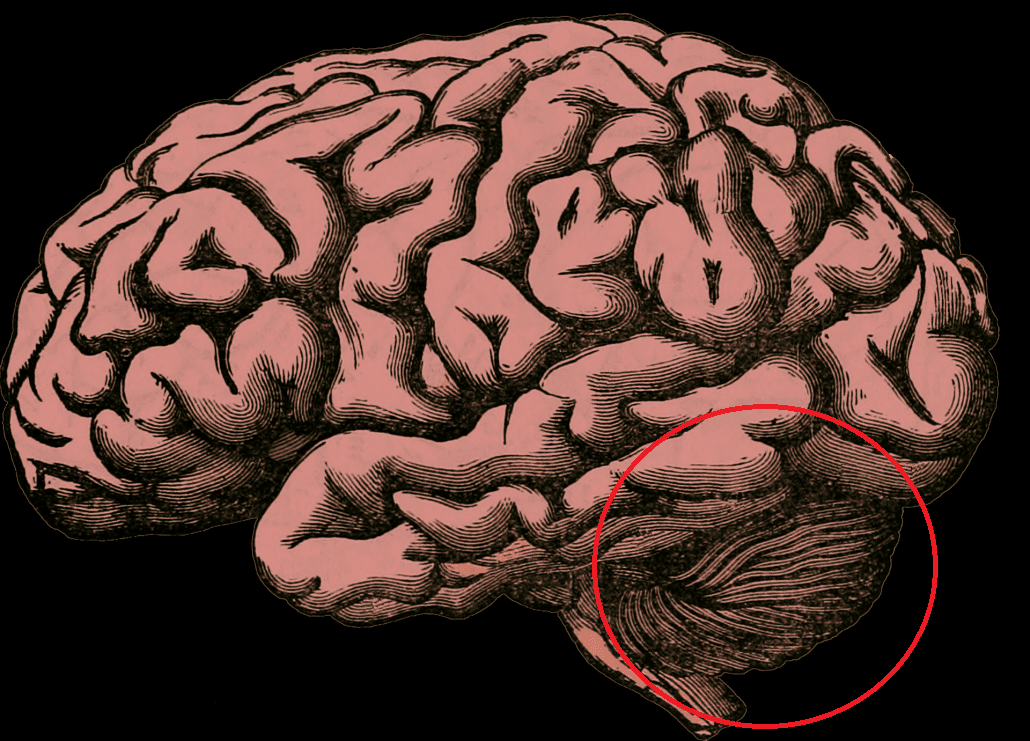

The Cerebellum is a brain structure partially concealed by the cortex. Classically it was thought that it was only in charge of harmonizing body movements, but for some years now it has become evident that it is involved in various cognitive functions. The Cerebellum has a shape similar to that of the brain, although a much smaller size. In fact, his name means “little brain.” It is divided into two hemispheres, and the portion of the cerebellum between them is called vermis. It is also the only part of the brain that has Purkinje Cells, a type of neurons essential for its functioning that allows the integration of the information it receives.

The Cerebellum is located in the back of the brain at the level of the brainstem bridge, under the occipital lobe (slightly above the nape of the neck). It binds to the rest of the brain through the lower, middle and upper cerebral peduncles, which are a set of nerve fibers that carry information from the rest of the body to the Cerebellum (afferent), or from the Cerebellum to the rest of the body (efferent). In fact, if it weren’t for the cerebral peduncles, it would be separated from the rest of the brain.